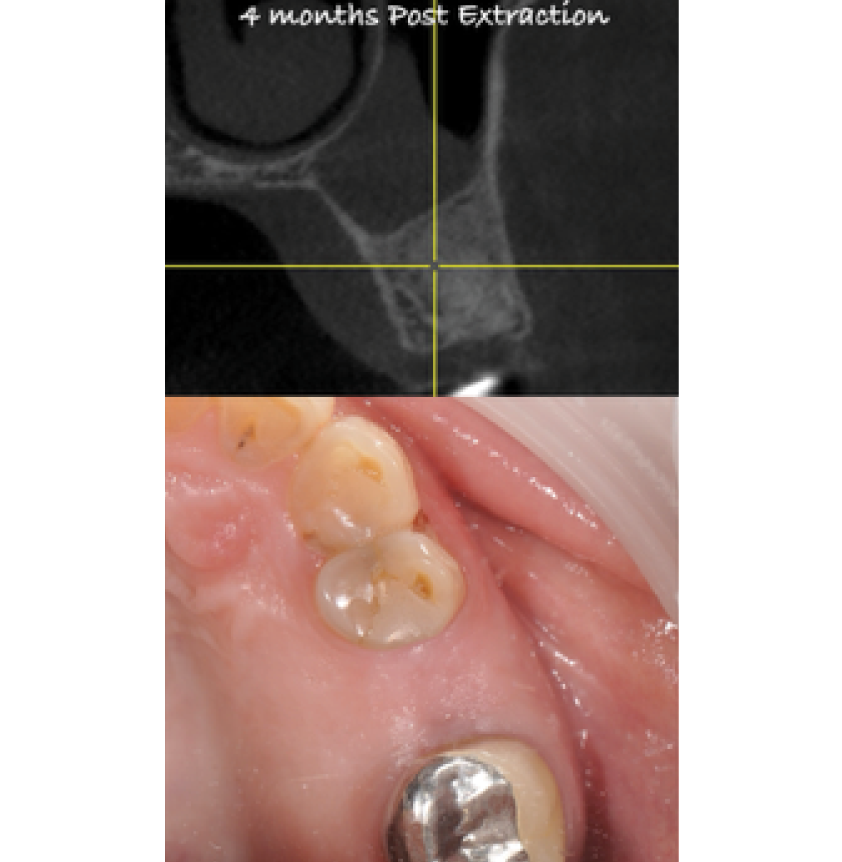

Director’s Clinical Cases

Director’s Clinical Cases